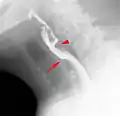

منظر جانبي لتضيق المريء بالوترة.

الوترة المريئية مع "ظاهرة الطائرة". رأس السهم على الفتحة الغير مكتملة من العضلة العاصرة للمريء.